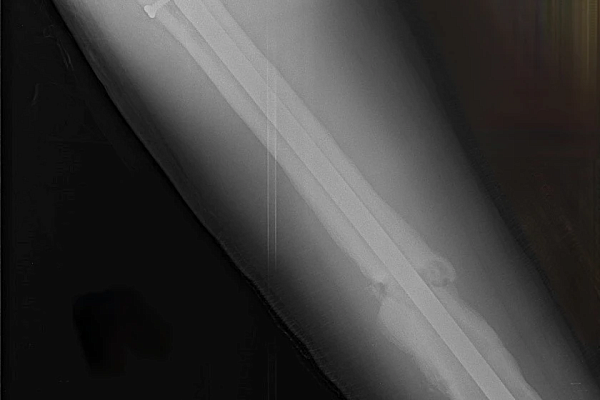

17‑летний Николай поступил к нам с осложнением после операции по поводу перелома бедра. Ранее ему был установлен интрамедуллярный штифт – для фиксации отломков кости с возможностью ранней нагрузки на конечность. Но прежде, чем перелом консолидировался, штифт сломался.

Врачам нужно было найти новое, более подходящее решение, при этом избежать травматичного открытого доступа и обойтись без больших разрезов. Задачу усложнял сломанный внутри кости штифт. Специального серийного устройства для его удаления малоинвазивным способом не существует. Чтобы пройти 40 сантиметров по костномозговому каналу, захватить и извлечь фиксатор, наши специалисты создали свою систему на базе имеющего набора проводников и экстракторов. Тщательное предоперационное планирование принесло желаемый результат в ходе вмешательства.

После успешного удаления прежней конструкции пациенту установили новую надежную систему - с учётом предыдущего опыта. Для этого понадобилось несколько небольших разрезов (не более 2 см). На второй день после операции Николай передвигался по отделению с помощью костылей, уже нагружая оперированную конечность. Сейчас он внимательнее прислушивается к рекомендациям, от выполнения которых зависит благополучие восстановительного периода.